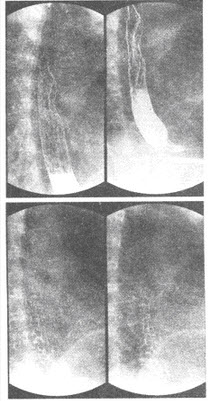

C.包裹性积液

患者,男,76岁,食管钡餐造影检查示食管壁张力降低,蠕动减弱,钡剂排空延迟,并在食管中下段见到串珠状充盈缺损影。钡餐检查如下图所示: